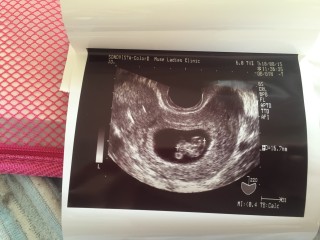

8w0d、CRL1.4cmです(*^^*)無事心拍確認できて一安心..。エコーを見た先生が、「おお~!大きくなったねぇ!赤ちゃん元気に動いてるで。」と言ってくれて、安心したのと嬉しいのとで泣けました(;_;)赤ちゃんも元気なのを見せるためか、大の字のポーズしてくれました(笑)すくすく育ってくれますように!

体外受精で授かりました。 1週間で、10ミリ以上大きくなってたのには驚きました! 右側が頭で、手足も見えてます(^^) 今日で出産予定日も決定しました。 今まで、胎芽は小さめだったし胎嚢は潰れてるし出血が続くしと、心配ばかりしてました>_< それでもキチンと育ってくれてありがとう!

頭と胴体がはっきりしてきました。四週間前は4ミリのただの丸しか見えなかったのに、よくここまで大きくなるもんだと感心しかできません。 一週間で倍の大きさになったのも驚きです。頑張って大きくなってくれてるので、私も食生活に気をつけたいと思います。赤ちゃんの大きさは16.7mmです。